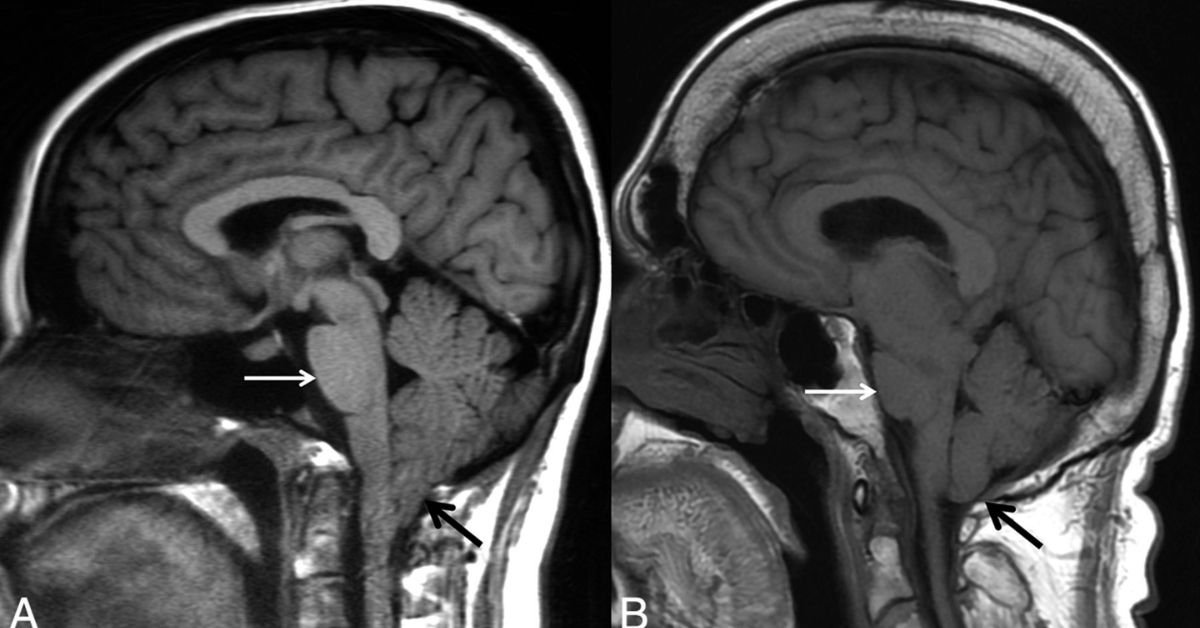

When this fluid leaks, the pressure inside the skull drops, causing the brain to shift slightly downward. This leads to a distinctive type of headache known as an orthostatic headache, which changes with posture.

- MRI of the brain and spine to detect signs of low CSF pressure